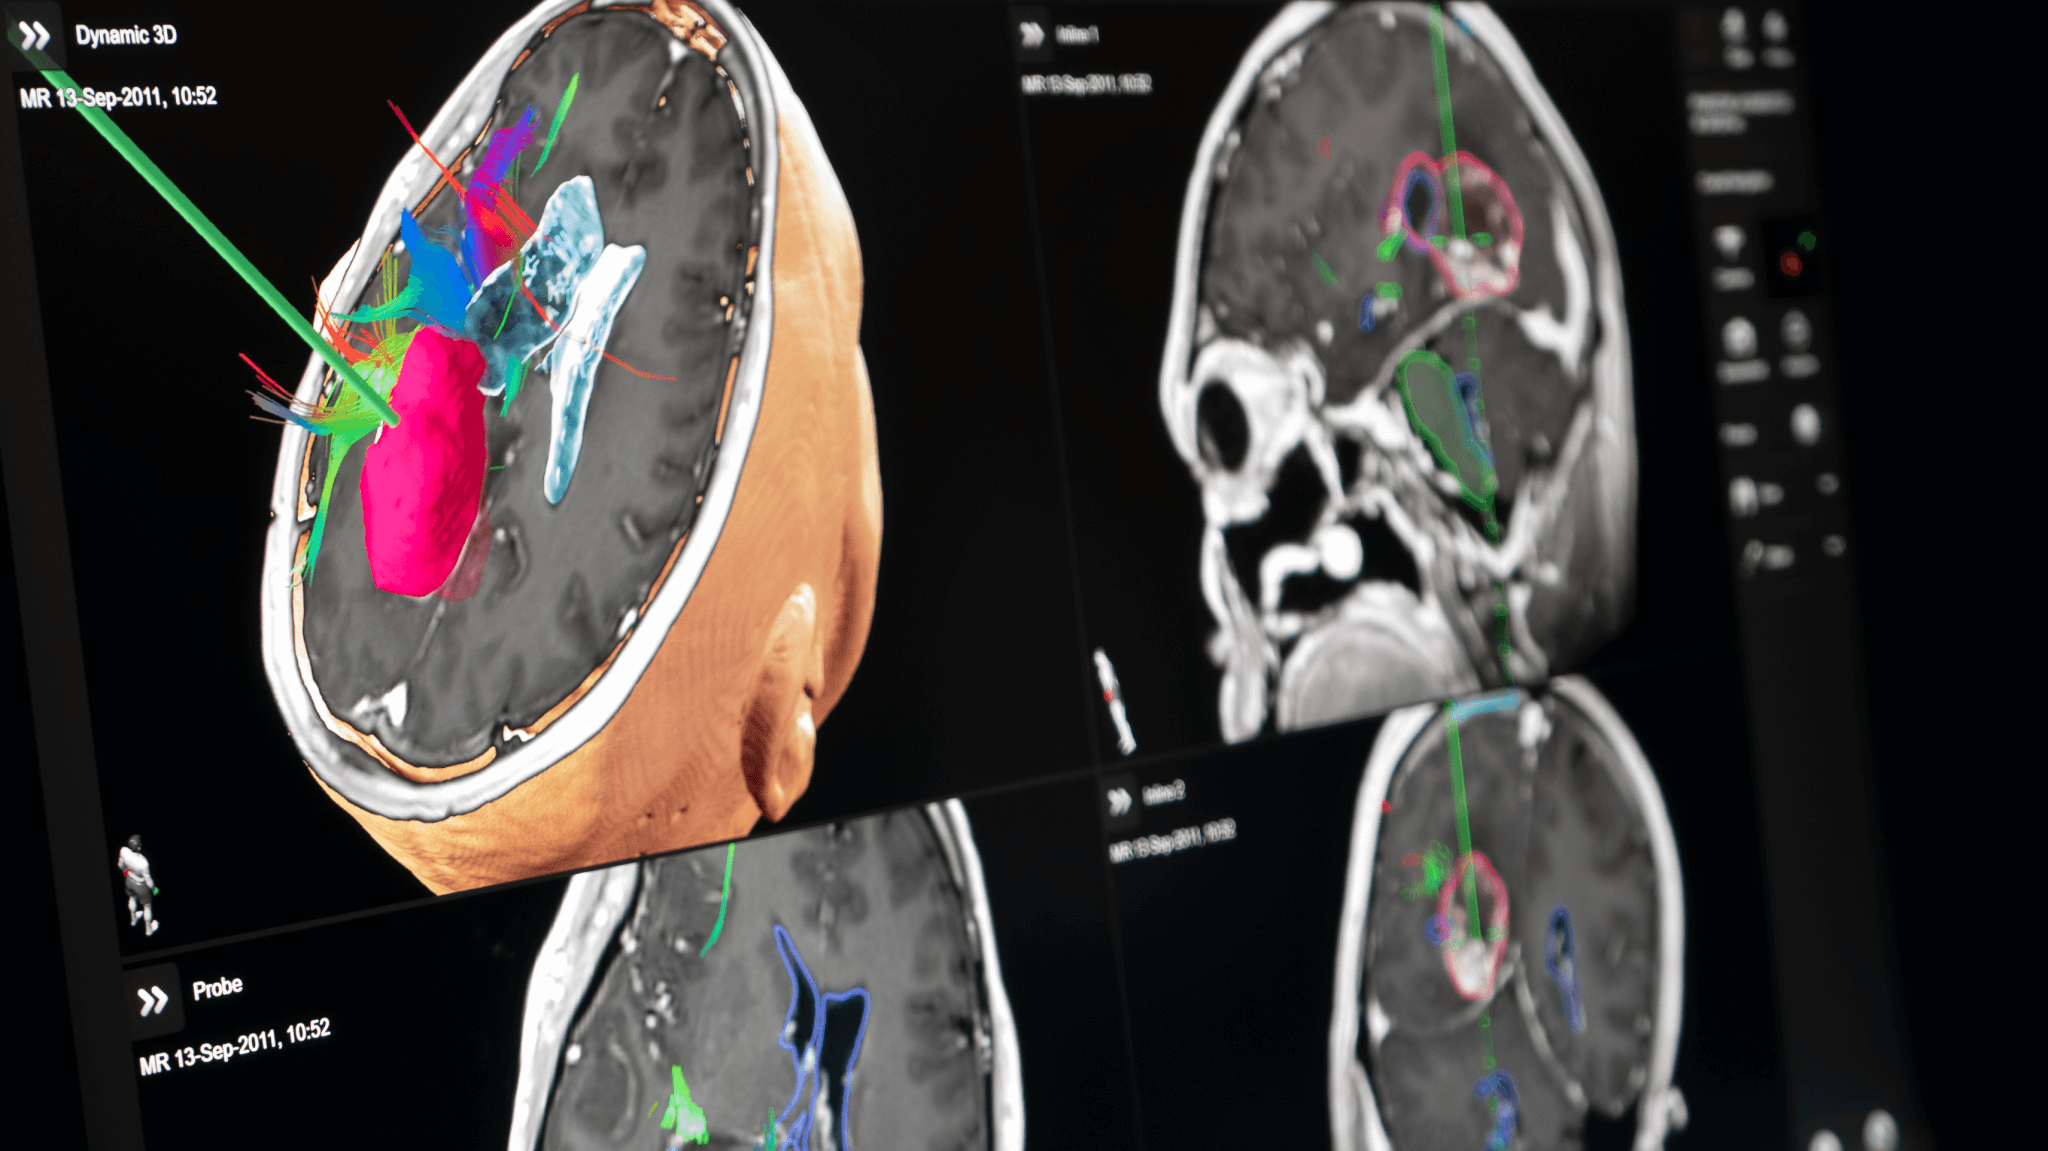

Brainlab neuronavigation combines ease of use with extended functionality tailored to surgeons’ needs